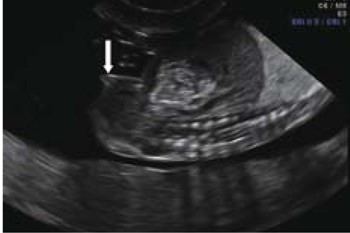

يعتمد التشخيص الجنسي للجنين على العلامة السهمية وهي اتجاه الحديبة التناسلية - يشير الاتجاه الصاعد إلى جنين ذكر، والاتجاه الهابط يشير إلى جنين أنثى

هنا يظهر جنين أنثى